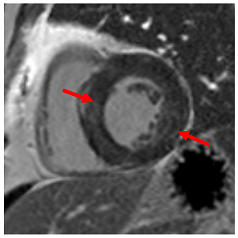

The differential diagnosis of HHD includes hypertrophic cardiomyopathy and its phenocopies (e.g., Fabry’s disease, mitochondrial disease); valvular heart disease (sub-valvular, valvular, and supra-valvular aortic stenosis); pseudohypertrophy (amyloidosis (Table 4A); sarcoidosis (Table 4B)); and the so-called athletic heart, among others. Imaging can plan an important role in elucidating the cause of LVH [47], especially in patients with dual-presence arterial hypertension/HHD and another cardiomyopathy associated with LV hypertrophy.

Example images of various differential diagnoses of hypertensive heart disease.

Cardiovascular magnetic resonance (CMR) uniquely allows tissue characterisation to be undertaken and as such, can readily differentiate hypertensive LVH from causes of pseudohypertrophy or thickening of the left ventricle due to myocardial infiltration with amyloid (Table 4A) or sarcoid (Table 4B) [47].

In clinical practice, the differentiation of hypertrophic cardiomyopathy from hypertensive LVH is a frequent and difficult challenge, especially as the two pathologies frequently coexist. Hypertrophic cardiomyopathy is typically characterised by asymmetrical LVH, usually involving the septum, but any myocardial segment can be involved [54]. Hypertensive LVH often causes concentric LV remodelling, but asymmetrical LVH is not infrequent, and concentric hypertrophic cardiomyopathy is well-described particularly in non-sarcomeric phenocopies (Table 4D), so the pattern of remodelling alone may not be helpful unless it disproportionately affects, for instance, apical segments that do not hypertrophy in isolation in patients with HHD [55,56]. Patients with sarcomeric HCM also frequently develop a reverse septal curvature morphology with a loss of concavity of the septal endocardial surface (Table 4E,F) [57]. Other features that may point towards HCM as opposed to hypertensive heart disease include ancillary abnormalities such as elongation of the anterior leaflet of the mitral valve [58]; protrusion of the anterior leaflet into the LV cavity–26 mm or more (“night cap” mitral valve) [59]; the presence of numerous myocardial crypts [Table 4G] [59] (isolated myocardial crypts are likely within normal limits [60]); apical displacement of the papillary muscles; anteromedial displacement or duplication of the anterolateral papillary muscles; apico-septal muscle bundles (Table 4H) [61]; and accessory papillary muscles or anomalous direct insertion of papillary muscles onto the mitral valve [62]. Systolic anterior motion of the anterior leaflet of the mitral valve and the associated posteriorly directed MR and left ventricular outflow tract obstruction are more frequently seen in HCM than hypertensive heart disease but can occur in both settings, particularly if there is hypertension and isolated basal septal hypertrophy with hyperdynamic LV contractility in the elderly [63]. Some degree of LGE can be seen in approximately two-thirds of patients with HCM, most often in the areas of maximum hypertrophy [64]. The pattern and extent of enhancement are often very heterogeneous within as well as between patients [65]. Diffuse patchy mid-wall enhancement is frequently seen in advanced hypertensive heart disease with poor blood pressure control (Table 4I) but equally can be seen in HCM [47]. However, very dense organised fibrosis is more commonly seen in the latter, particularly in the so-called burned-out phase (Table 4J).